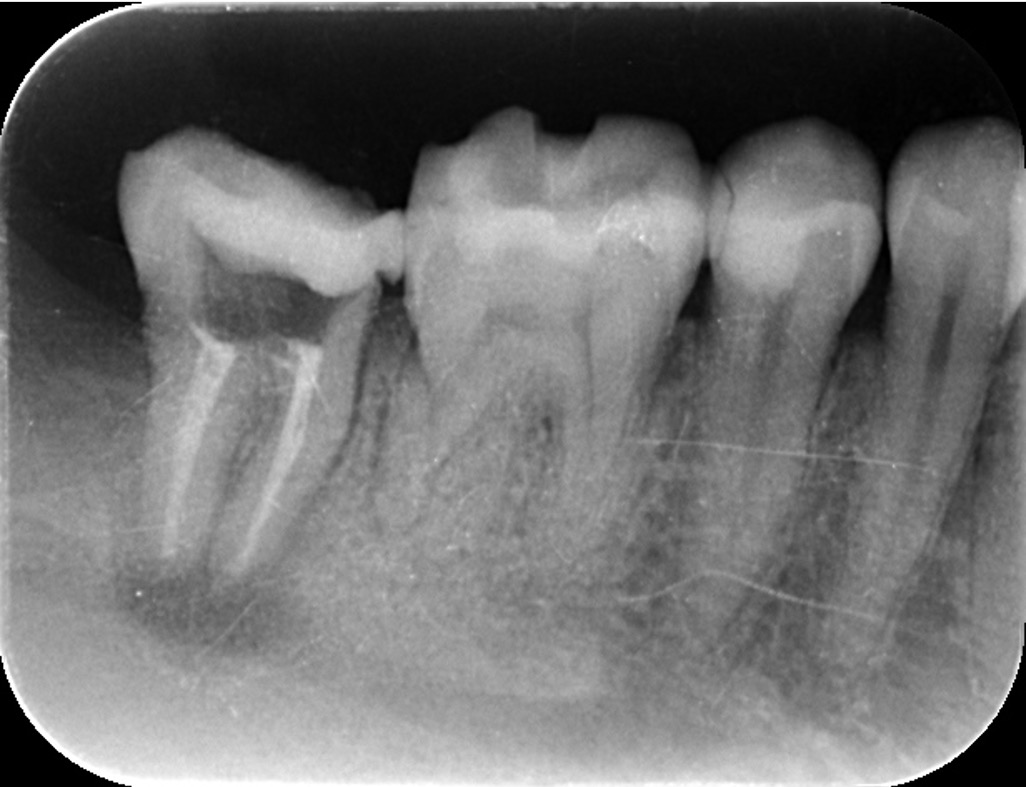

こちらは虫歯で神経を取らないといけなくなりましたが、何度治療しても痛みが消えないと言うことで当院にいらっしゃいました。度重なる治療で歯の神経のあった場所がかなりひろげられており、また根の先端も破壊されている状態でした。ですので、痛みが消えないのです。

肉眼では根の先端は見ることができませんがマイクロスコープでは見ることができます。根の先端をこれ以上破壊しないように清掃して歯の神経があった場所にお薬を詰めることができました。根の治療後、かぶせ物までして半年たっても痛みがありません。

レントゲンを見ていただいて、歯の先までしっかり白いお薬が入っているのがわかります。